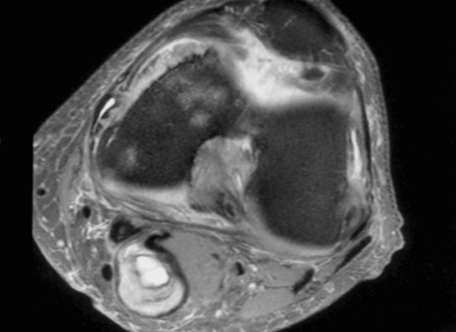

Heterogenous mass, low signal intensity T1, high signal intensity T2

- may have characteristic triple signal intensity

- area hyperintensity, isointensity and hypointensity

Knee

Heterogenous mass, not communicating with joint

DDx Baker's cyst

- semimembranosus

- communicates with joint

- between semimebranosus tendon and medial head gastrocnemius